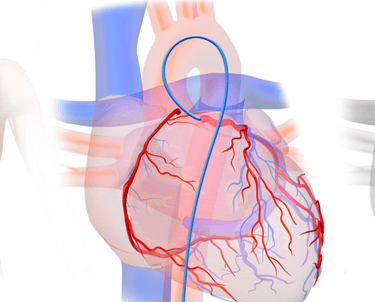

Coronary Angiography / कोरोनरी एंजियोग्राफी

A test to detect blockages in heart arteries using dye and X-ray.

Procedure to open blocked arteries and restore blood flow using balloon and stent.

Coronary Angioplasty (PTCA) / कोरोनरी एंजियोप्लास्टी